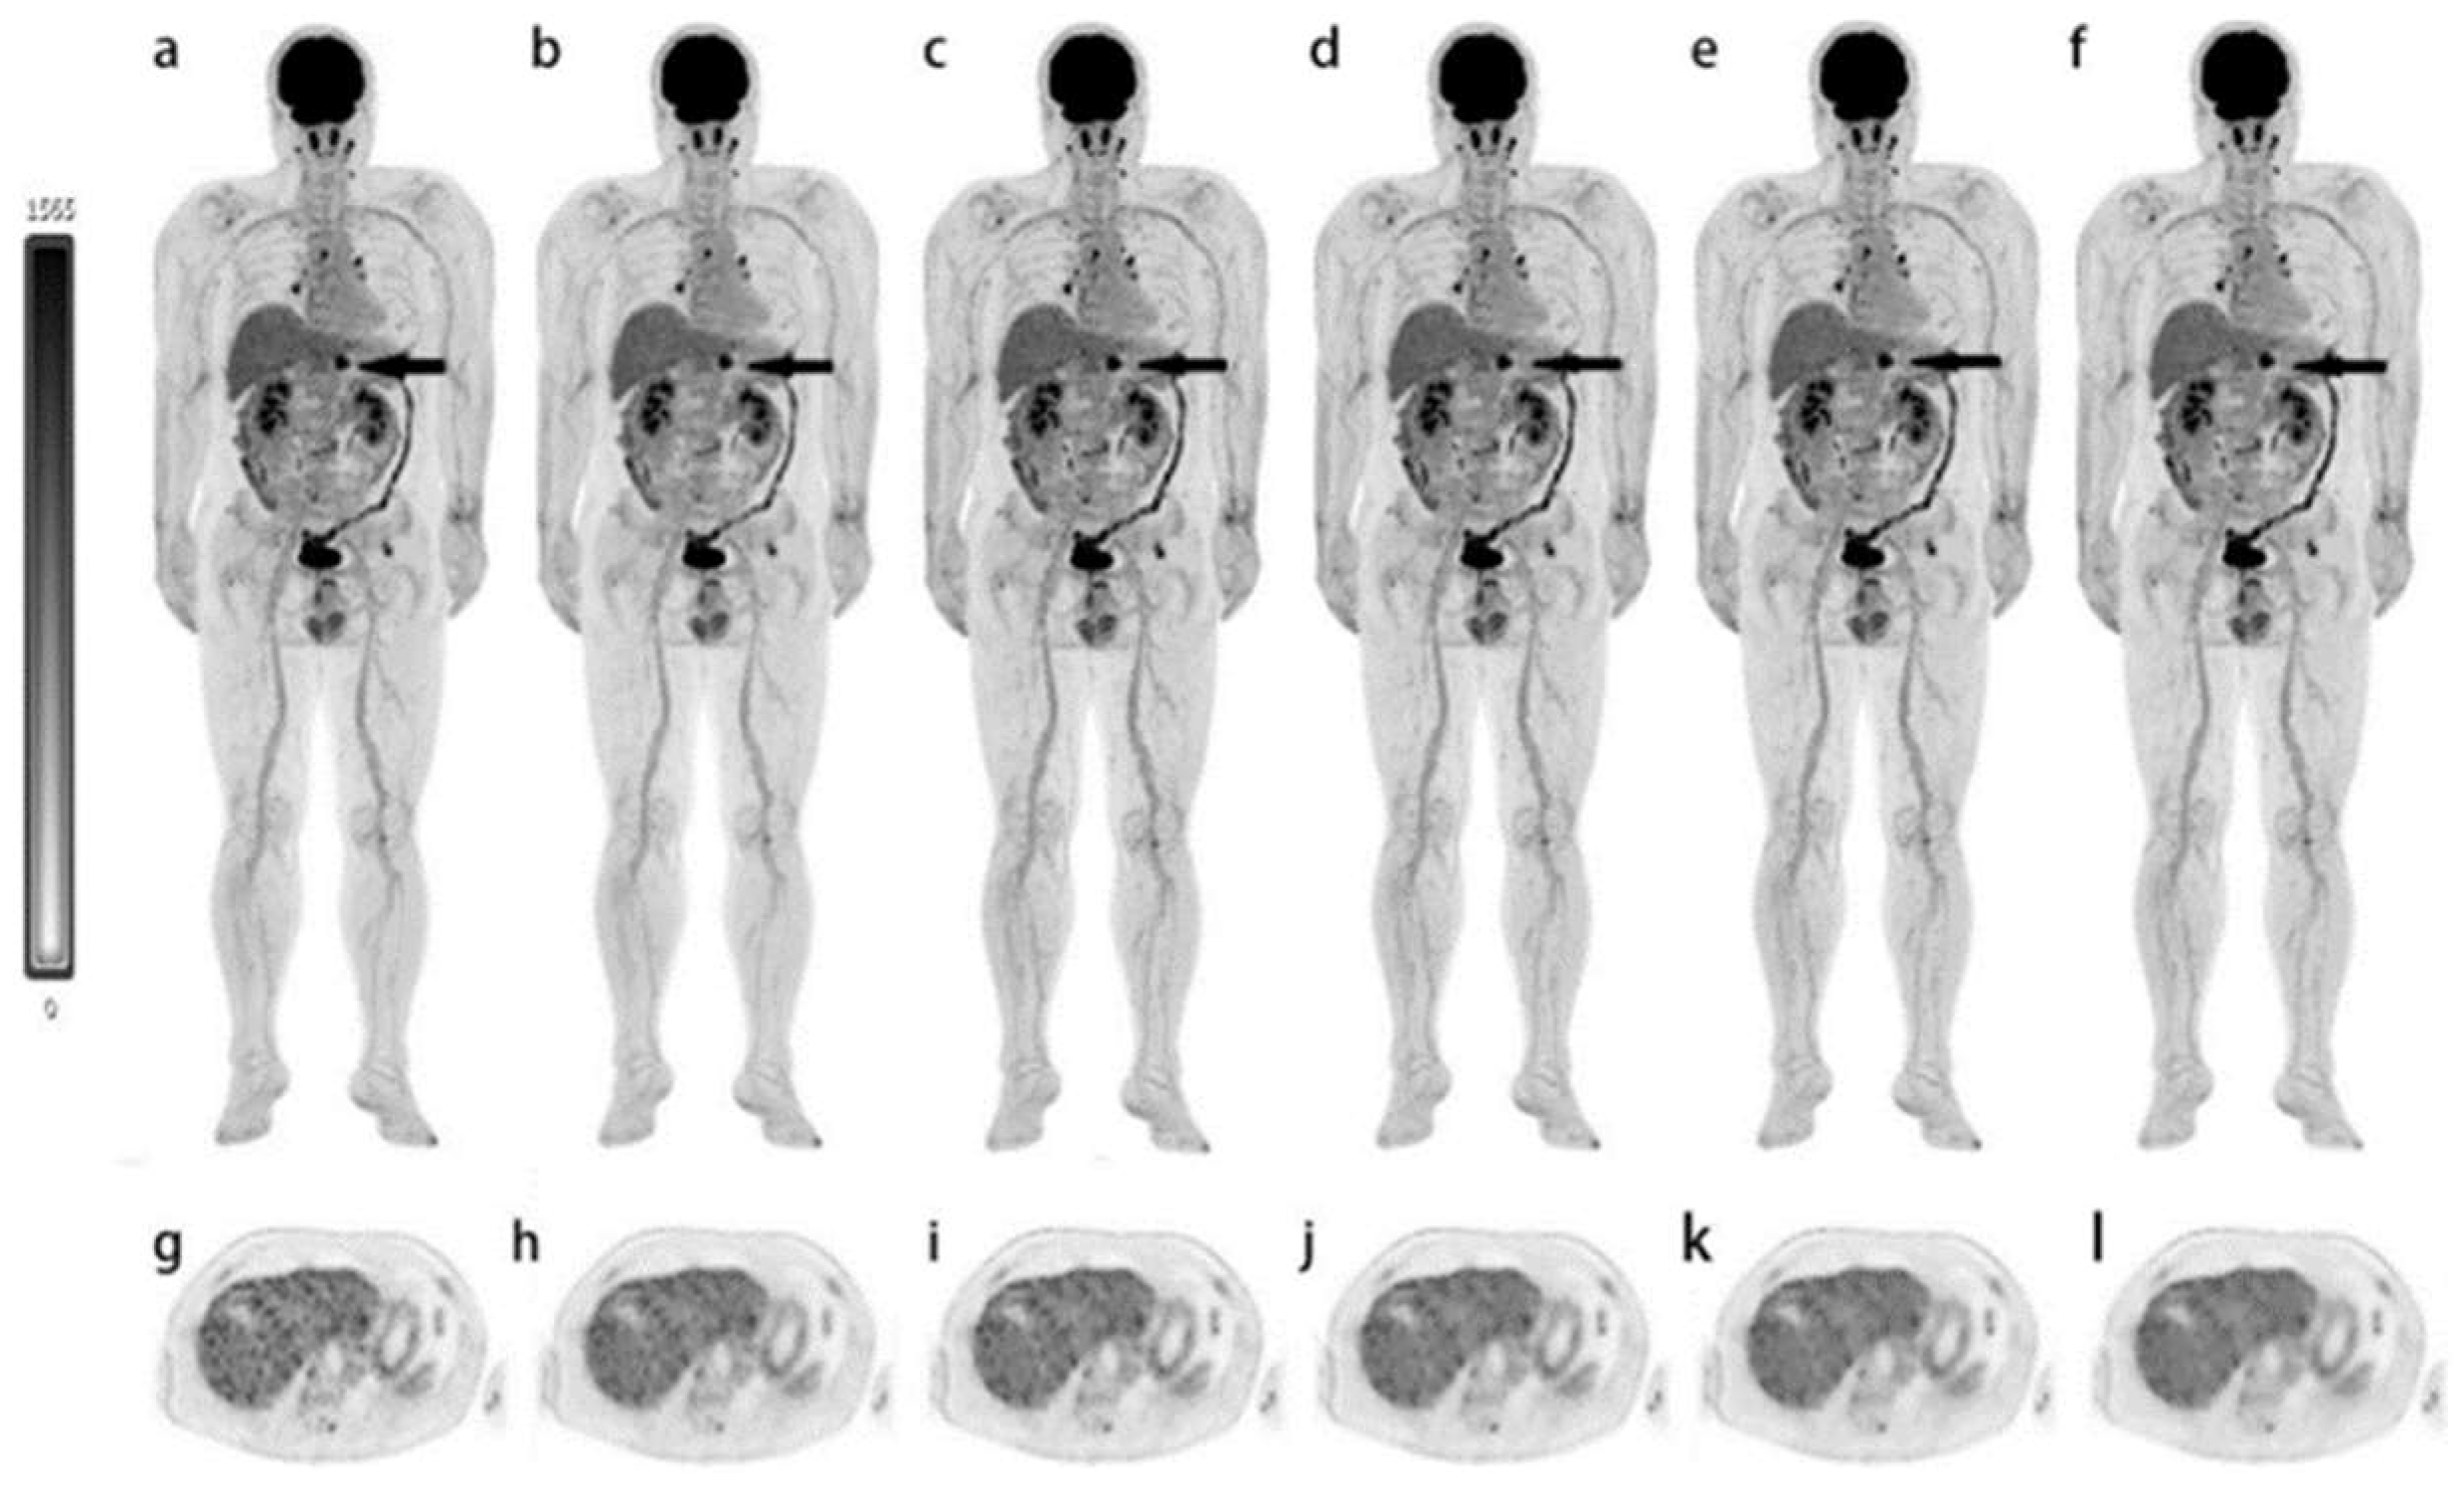

- Mohr, P.; van Sluis, J.; Providencia, L.; van Snick, J.H.; Lub-de Hooge, M.N.; Willemsen, A.T.; Glaudemans, A.; Boellaard, R.; Lammertsma, A.A.; Brouwers, A.H.; et al. Long Versus Short Axial Field of View Immuno-PET/CT: Semiquantitative Evaluation for (89)Zr-Trastuzumab. J. Nucl. Med. 2023, 24, jnumed.123.265621. [Google Scholar] [CrossRef]